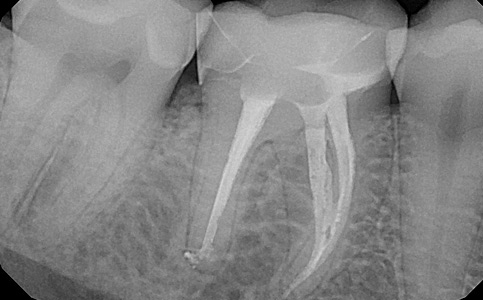

Po dokładnej diagnostyce ząb zakwalifikowano do leczenia endodontycznego. Leczenie przeprowadzane zostało przez naszego specjalistę pod mikroskopem.

Zobacz efekty przeciągając suwak w prawo lub w lewo.